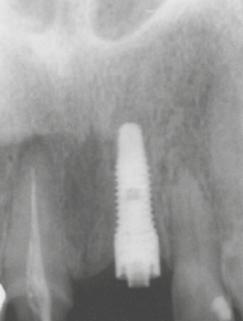

19. ábra: A kész restaurátumok a szájban, beragasztás után. 20. ábra: A kontroll panorámaröntgen felvétel.

deti fázisában a gingivális szinten kialakult hemidezmoszomális tapadást, anélkül, hogy bármilyen módon kompromittálná az esztétikát ebben az igen érzékeny régióban� Az egyedileg leplezett protetikai fej és korona elkészülését követően a szomszédos fogak helyreállítása is befejeződött (18. ábra)� Átadáskor a korona cementezésével kitűnő esztétikai eredményt értünk el (19. ábra)� Az elért zárást és a BioBlock koncepciót követve, már az implantátum behelyezésétől kezdve a formázott ínyt sikeresen megőriztük a végleges fogpótlás elkészültéig� A kezelés befejezését dokumentáló panoráma röntgenfelvétel (20. ábra) a restaurátum és a csont stabil állapotát mutatja�